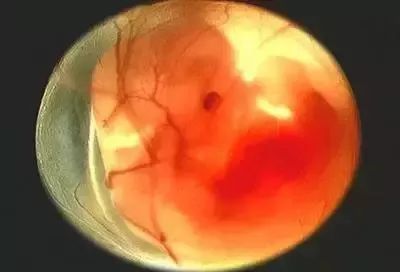

两个月:胎儿长约1.6厘米,大致相当于芸豆大小,胚胎形状最初有人的外表。整个身体的一半,胚胎的脸已经出现,舌头和未成熟的牙龈,手臂上的手指,膝盖,脚踝和脚趾,胚胎被一层薄薄的皮肤覆盖;大脑和性器官开始发育,尽管你可能很清楚D的性别。敖包宝宝,但婴儿的外部生殖设备还没有完全开发。目前还不清楚你是否怀孕了男孩或女孩。此时心跳稳定,胃开始分泌消化液,肝脏开始产生血细胞;肾脏开始工作,并在出血中排出尿液;皮肤敏感性增强,触觉刺激可反应。

三个月:胎儿的身体为7-9厘米,重约20克,与4-7周相比,胎儿增加了3.4倍以上,躯干和腿部全部发育,头部明显较大,下颚和颊部发达,更重要的是鼻子、嘴唇、根。声带已经长了,脸部更像脸部,眼睛已经被比较了。眼睑生长。它能对外界刺激作出反应。如果你用手戳你的胃,它甚至会移动,但在几周内,你就感觉不到他的活动。胎儿肠生长很快,其中一些进入脐带。他们开始转移到腹腔。胎儿的肾脏分泌尿液进入膀胱。